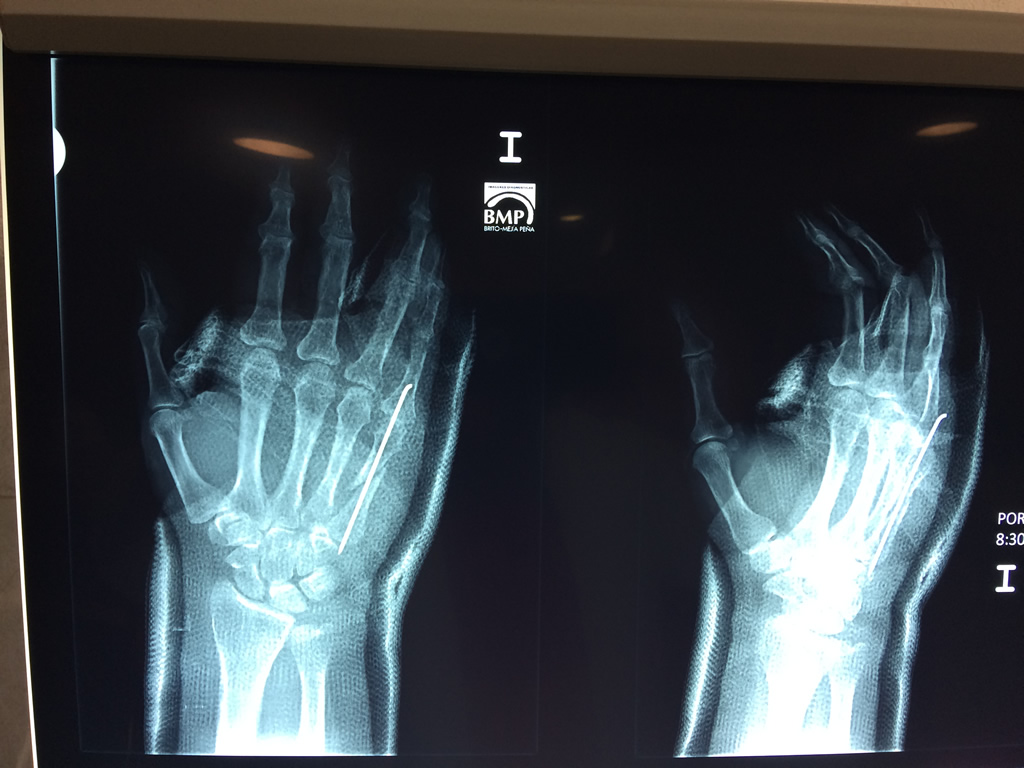

Cirugías de Muñecas

Los procedimientos más comunes en cirugía de la mano son aquellos destinados a reparar traumatismos, incluyendo lesiones de tendones, nervios, vasos sanguíneos, y articulaciones; huesos fracturados; y quemaduras, cortes, y otros daños de la piel.